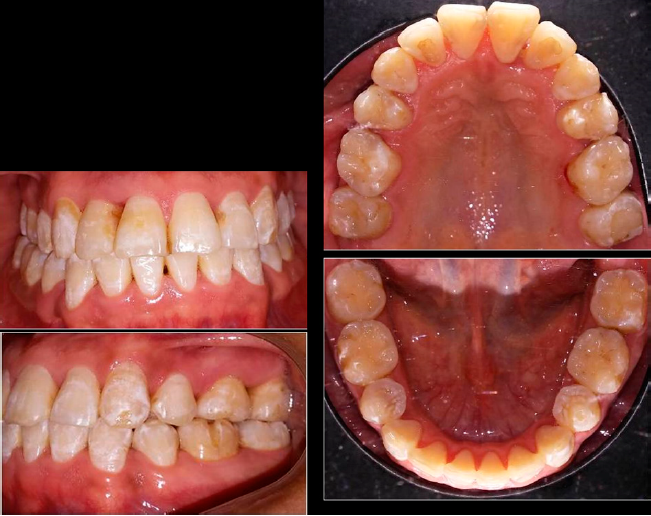

En el análisis facial se determinó una paciente dolicofacial con el tercio inferior aumentado, exposición disminuida de los dientes anteriores superiores al sonreír y perfil recto (Figura 1). A la exploración clínica se identificó dentición permanente con ausencia de los dientes 34 y 44, periodonto reducido estable, mucosa bien irrigada, frenillos bien implantados, líneas medias no concordantes, apiñamiento superior severo e inferior moderado; dientes 13 y 23 en supraoclusión Clase III molar, y mordida cruzada unilateral (Figura 2). Se solicitaron auxiliares diagnósticos incluyendo ortopantomografía y radiografía lateral de cráneo (Figura 3).

Se llevó a cabo la retracción del segmento anterosuperior inicialmente con arcos 0.019” x 0.025” SKL para lograr el cierre de espacios (Figura 5), seguido de la colocación de arcos 0.019” x 0.025” TMA en la arcadas superior e inferior (Figura 6). Al término del tratamiento se colocó retenedor fijo de canino a canino con alambre trenzado 0.175”. Al finalizar el tratamiento, se lograron clases molar y canina I en ambos lados, cierre de espacios, buena intercuspidación y alineación y nivelación dental, logrando así contribuir a mantener la salud periodontal (Figura 7). Asimismo, los ejes axiales de los incisivos mejoraron al igual que la topografìa ósea como puede observarse en las radiografías finales (Figura 8).